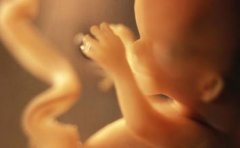

孕期做彩超检查对孕很多孕妈来说都不陌生,利用三维彩超表面成像就...

三维彩超和四维彩超一样,都是诊断胎儿畸形的主要手段,那么,三维彩超...

三维彩超是立体动态显示的彩色多普勒超声诊断仪,它的作用和普通的...

生个健康的宝宝是每位准妈妈最大的心愿,三维彩超不仅能够监测宝宝...